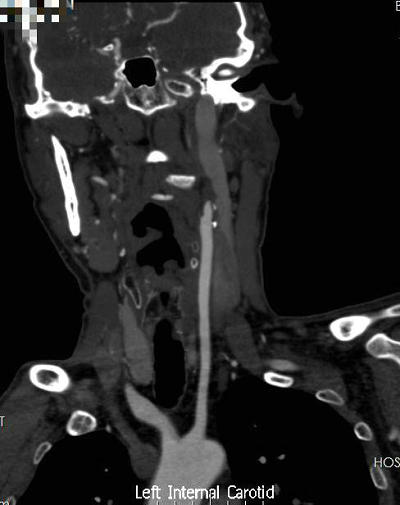

▲ 术前CTA

患者赵某今年47岁,近2个月间断出现左眼视物模糊,伴发头晕和右手无力,2天前突发左眼失明,在医院眼科治疗期间发现罪魁祸首竟是左颈内动脉闭塞,后转至血管外科行手术治疗。经过完善的术前检查、评估及充分的手术准备,三个优秀团队协同奋战三个多小时,手术顺利完成。患者术前评估ABCD2评分为6分,提示卒中高发风险。术后右侧肢体无力及头晕症状明显缓解,ABCD2评分降为2分,极大降低了远期脑卒中发生风险。遗憾的是,由于该患者来院诊疗时间较晚,出现了左眼的不可逆的视力损伤,最终视力无法恢复正常。在此,也需要提醒广大患者朋友,出现各种不适症状切勿延误治疗,避免错过最佳治疗时机。本例患者的成功救治,再次体现了郑州大学五附院血管外科对疑难病症的高超诊疗能力,体现了多学科协同作战的独特优势。